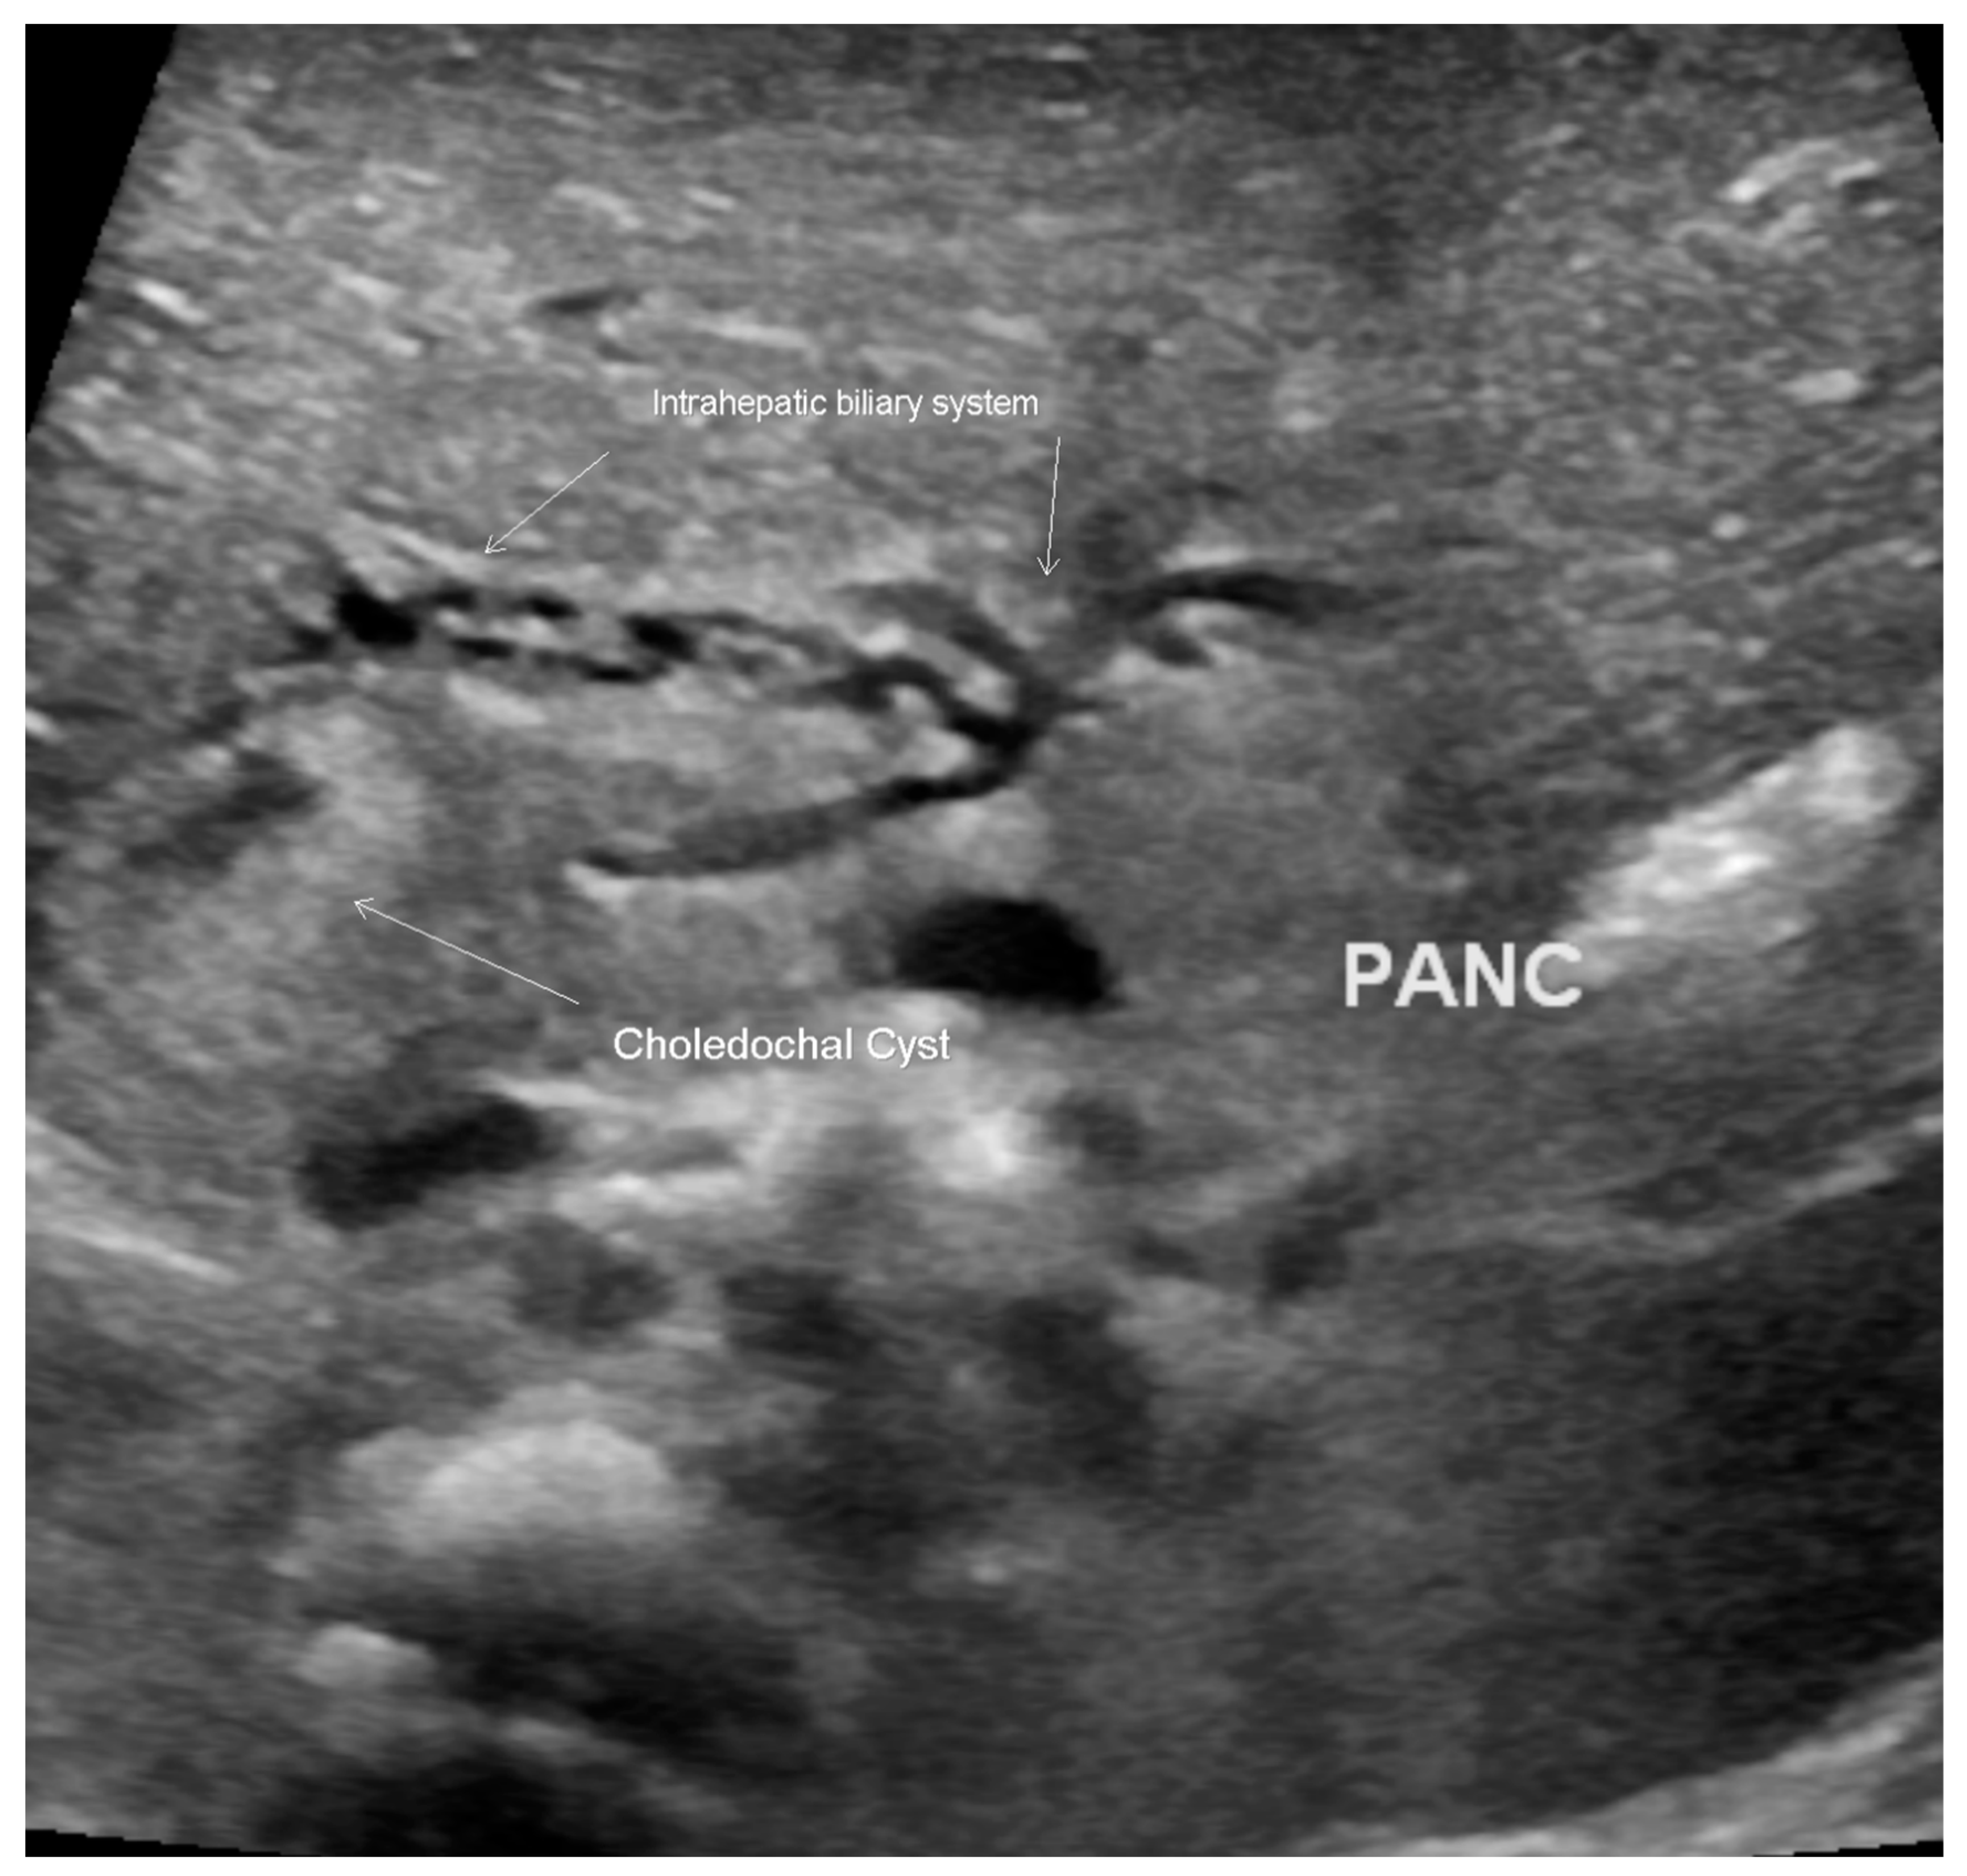

Figure 3.

Ultrasound scan of the abdomen, revealing a choledochal cyst with dilatation of the intrahepatic biliary system.